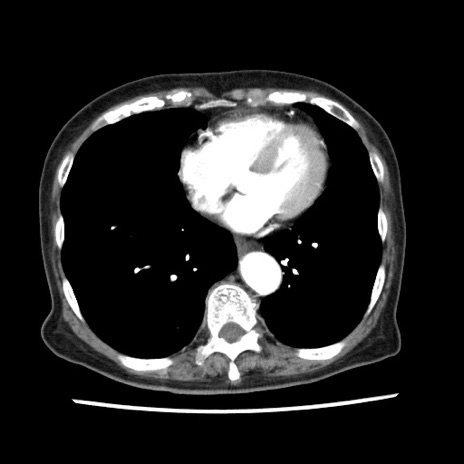

冠状断像

【症例】80歳代女性

【主訴】腹痛

【現病歴】8時間前から腹痛あり来院。

【既往歴】糖尿病、脂質異常症、子宮体癌にて子宮全摘術

【身体所見】意識清明・会話良好だが腹痛で苦悶様、全腹部にわたって反跳痛と圧痛あり

【データ】WBC 13600、CRP 0.14、LDH 224、CK 90